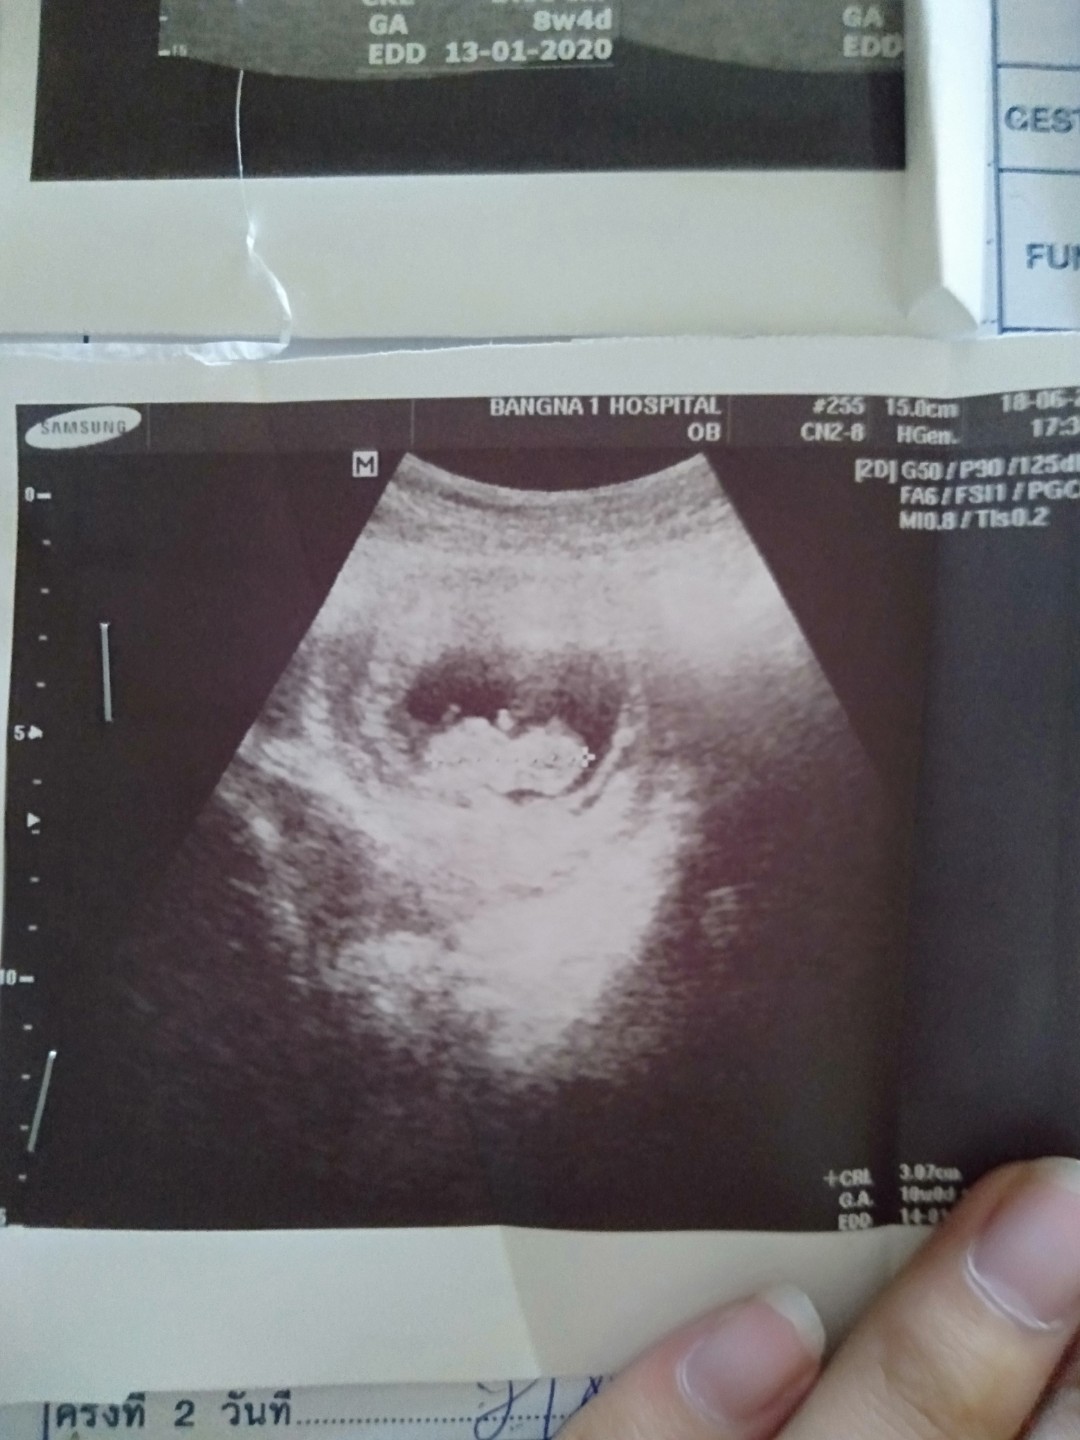

9 week 4day ค่ะ